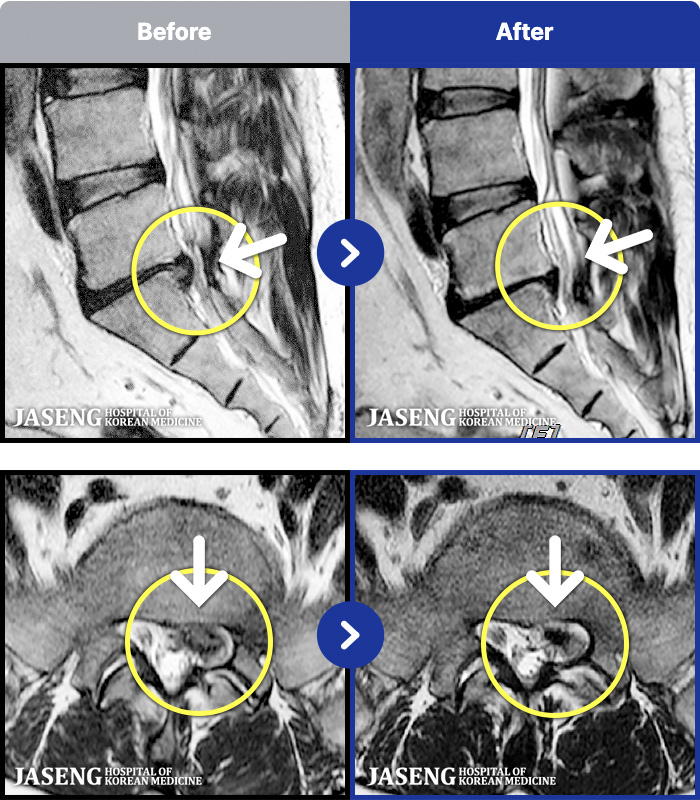

MRI ġ

1,245 MRI ũ ʸ Ȯϼ.